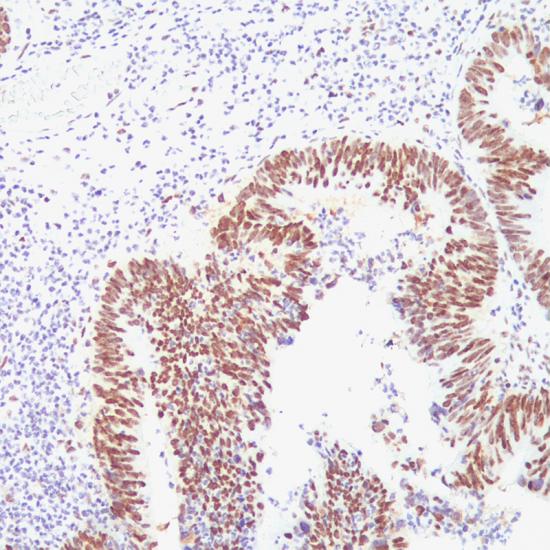

MSH2

MSH2抗體試劑(免疫組織化學(xué)) 閩廈械備20180076號

• 陽性部位:

細(xì)胞核

• 陽性對照:

結(jié)腸癌

G219-1129

MSH2是一種錯配修復(fù)基因,突變后會使細(xì)胞錯配修復(fù)功能缺陷,導(dǎo)致微衛(wèi)星不穩(wěn)定,使腫瘤易感。通常和MLH1、MSH6、PMS2一起用于腫瘤的研究。